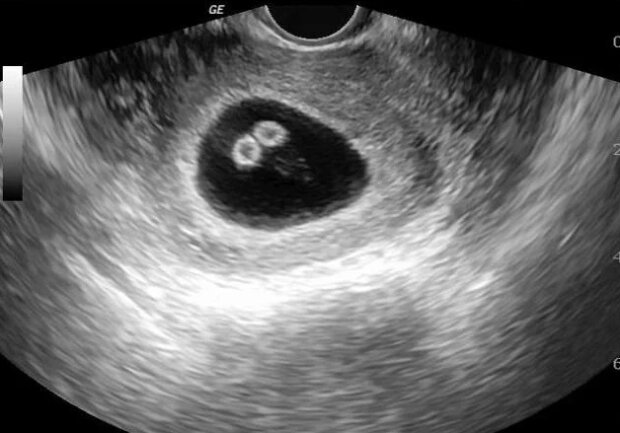

Ultrazvuk

Když bylo během ultrazvukového vyšetření potvrzeno, že žena měla pod srdcem čtyři děti, navrhlo se těhotenství ukončit. Budoucí matka však tuto myšlenku důrazně odmítla.